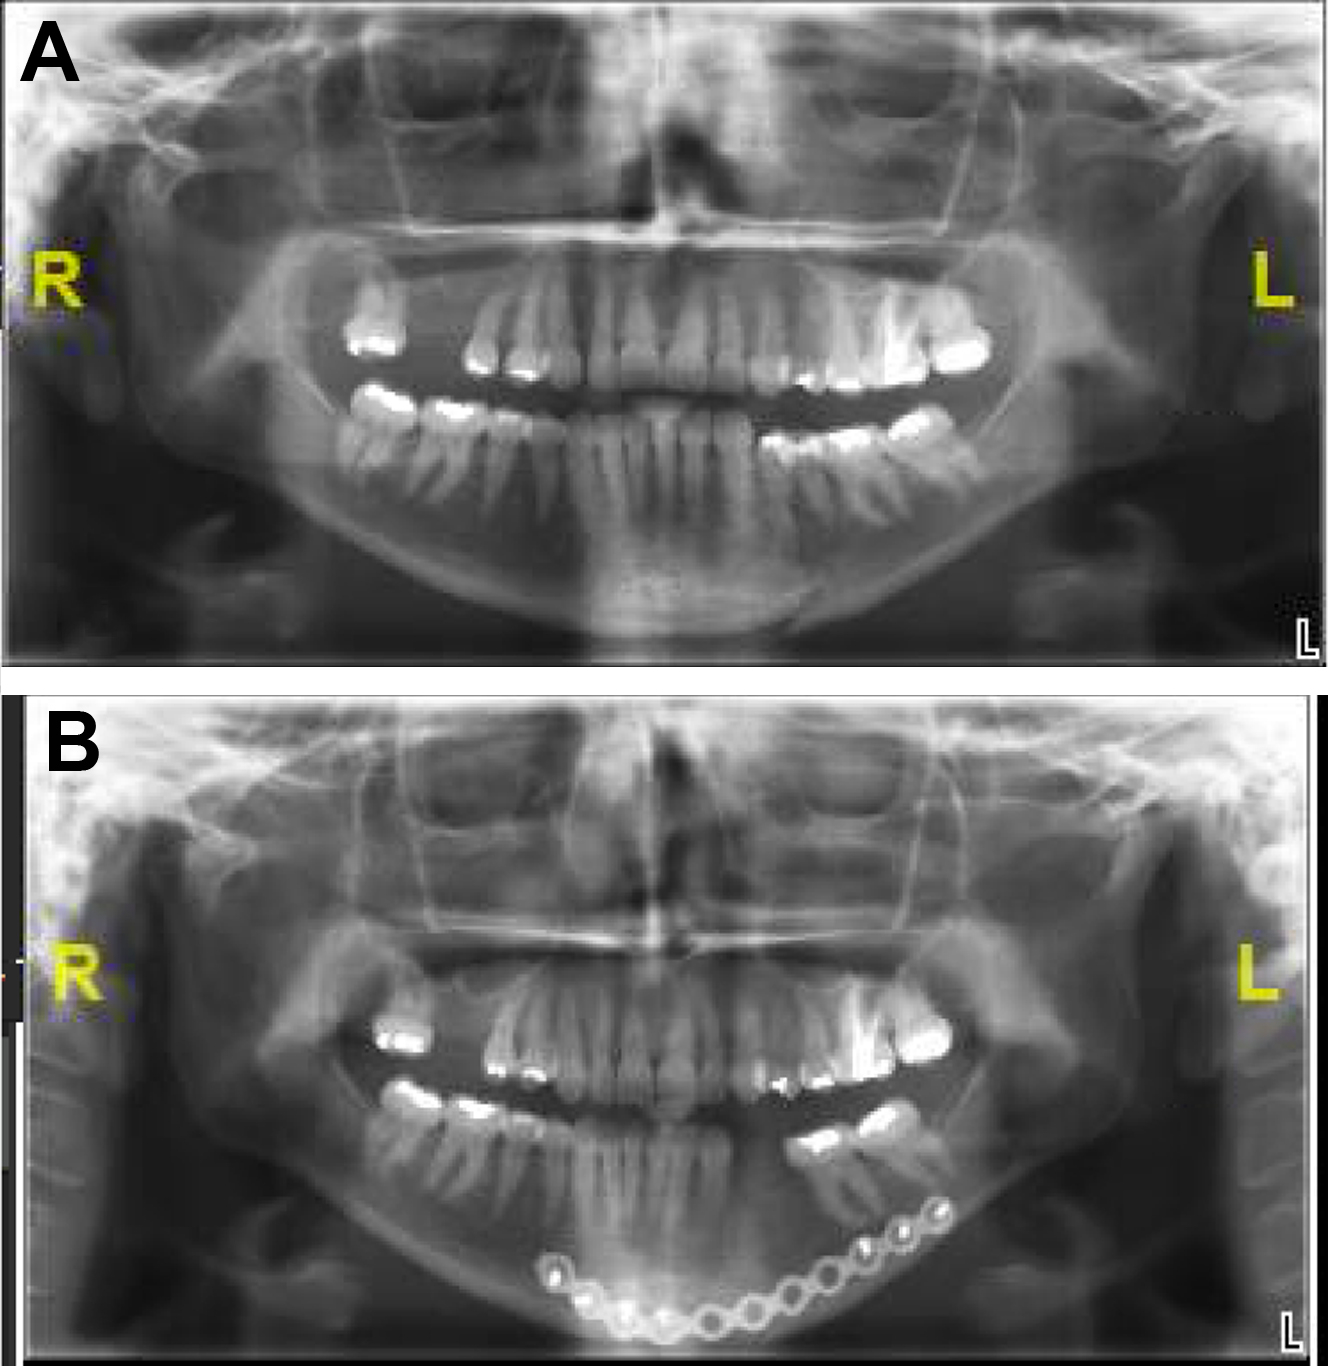

The gold standard for identification and evaluation of mandible fractures is a maxillofacial computed tomography (CT) with cuts at 1 mm or less. Three-dimensional reconstruction of CT scans facilitates understanding of geometric relationships and fracture fragment orientation. However, minimally displaced or hairline fractures may be missed due to volume averaging. The axial, coronal, and sagittal cuts should be carefully evaluated for every patient. Panoramic tomography (eg, panorex) may be used for evaluation of mandible fractures and involves lower cost and radiation exposure. Some surgeons may routinely use this modality of imaging, particularly for postoperative assessment of plating ( Fig. 5 ). However, the lack of 3-dimensional relationships makes appreciation of fracture angulation difficult. CT has higher sensitivity in fracture identification and decreased interpretation error.